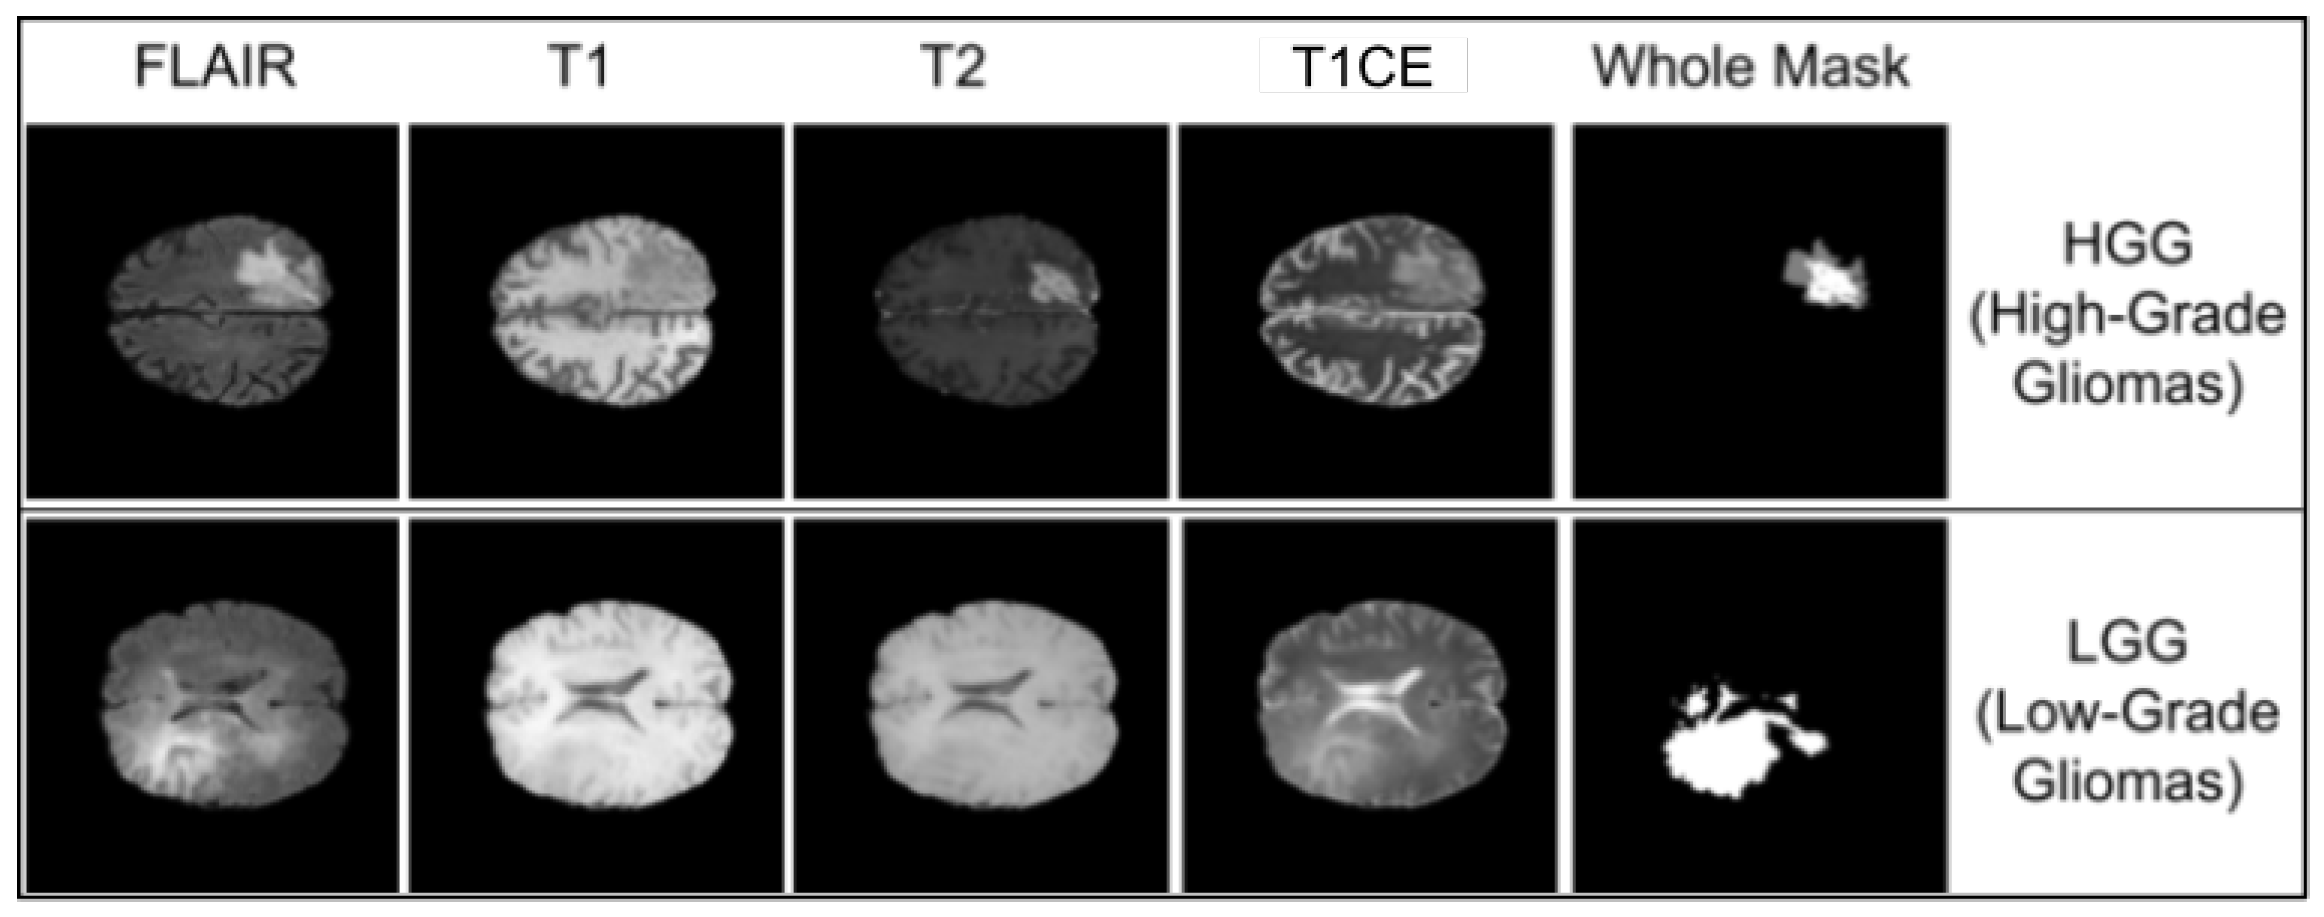

3.1.2. BraTS 2021 Dataset

- T1 emphasizes anatomical structures.

- T2 highlights fluid-filled regions.

- T1CE captures active tumor enhancement.

- FLAIR is sensitive to edema and non-enhancing tumor cores.

4.5. Evaluation on BraTS 2018: HGG and LGG Segmentation Performance

4.5.1. High-Grade Glioma (HGG) Evaluation

4.5.2. Low-Grade Glioma (LGG) Evaluation

4.8.1. HGG: Boundary Sensitivity and Modality Reliability

4.8.2. LGG: Homogeneous Boundaries and Compact Attention Spread

4.8.3. Comparative Observations: HGG vs. LGG